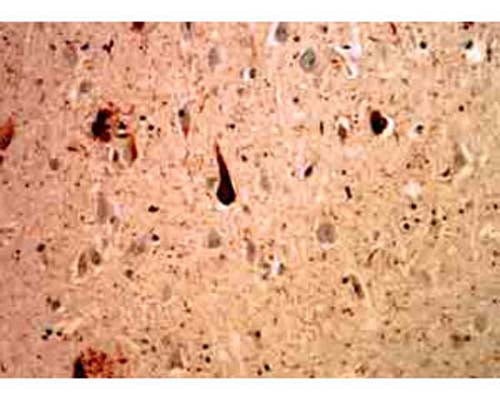

Mouse monoclonal antibody to Ubiquitin [Ubi-1] M-1404-100 staining of cerebral cortex of an Alzheimer patient. Neurofibrillary tangles and dystrophic neurites associated with senile plaques stain strongly with this antibody. In the center is a typical neurofibrillary tangle containing neuron.